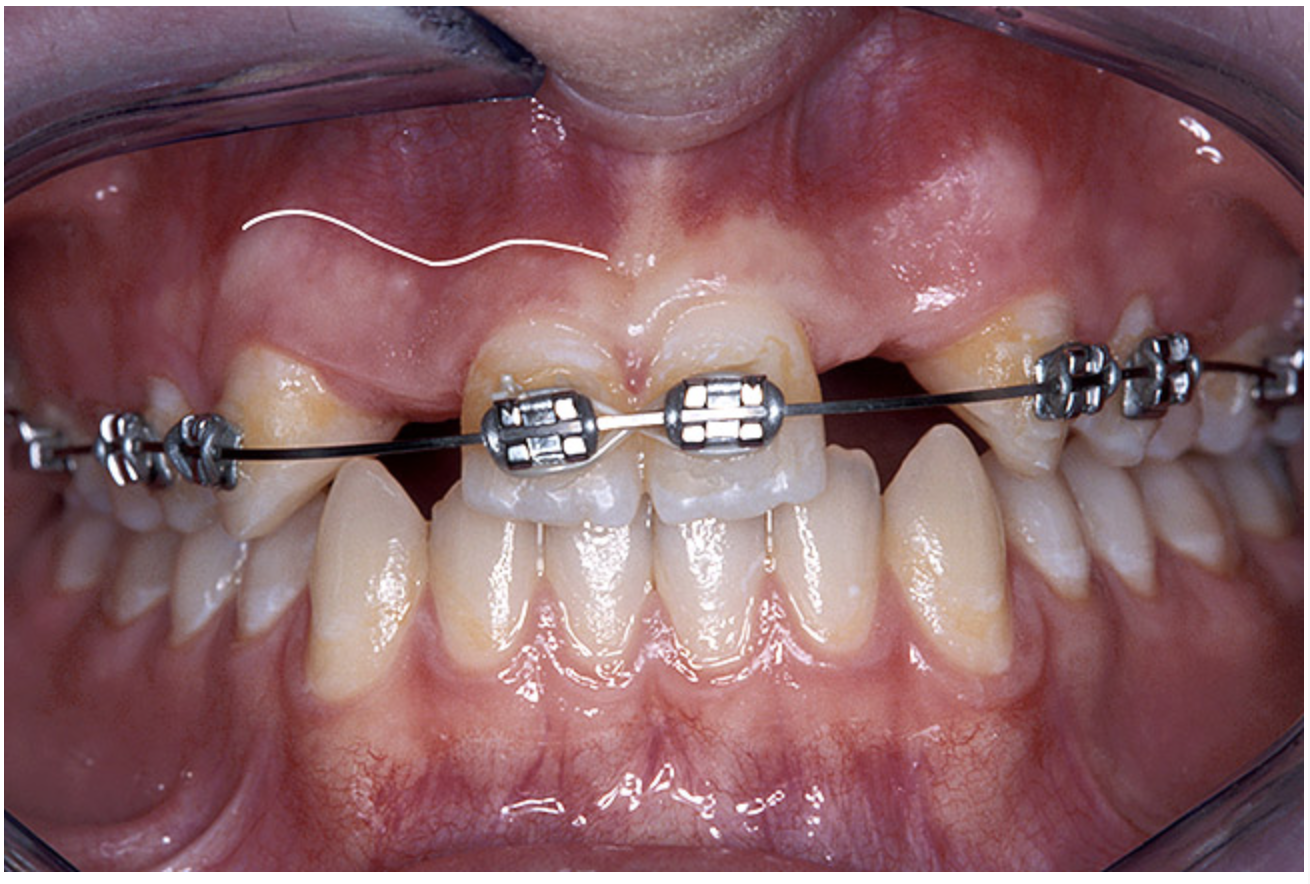

Before the day of surgery, the patient was seen by the orthodontist for the removal of the orthodontic brackets. The patient still was not pleased with the position of the two centrals, and it was determined that this would be addressed after implant placement (Figure 13A). The anatomical variations of the crestal tissue and lack of interdental papilla can be appreciated in the close-up views of the right and left sites (Figure 13B and 13C). There were no surprises on the day of surgery as all of the decisions were made during the planning phase, before the scalpel ever touched the patient. The occlusal view of the CT 3D model revealed the wider alveolar ridge on the right side and thinner crest on the left side (Figure 14A). This was confirmed when the full thickness mucoperiosteal flaps were elevated, and the underyling bone revealed (Figure 14B). The tooth-borne templates were designed to facilitate the drills and drilling sequence specific to the diameters of the predetermined implants (Figure 15A). Each template contained an embedded 5-mm long stainless steel tube, which was approximately 0.2-mm wider than each drill (just wide enough to allow for the drills to rotate freely). Once positioned over the natural teeth, the template was secure and offered precision accuracy in transferring the implant locations from the original software-designed plan, allowing the potential for internal and external irrigation (Figure 15B).

Figure 13a  Before implant surgery, the orthodontic brackets were removed, revealing (A) the position of the centrals, and (B, C) the anatomical variations of the crestal tissue and lack of interdental papilla.

Figure 13a

Figure 13b  Before implant surgery, the orthodontic brackets were removed, revealing (A) the position of the centrals, and (B, C) the anatomical variations of the crestal tissue and lack of interdental papilla.

Figure 13b

Figure 13c  Before implant surgery, the orthodontic brackets were removed, revealing (A) the position of the centrals, and (B, C) the anatomical variations of the crestal tissue and lack of interdental papilla.

Figure 13c